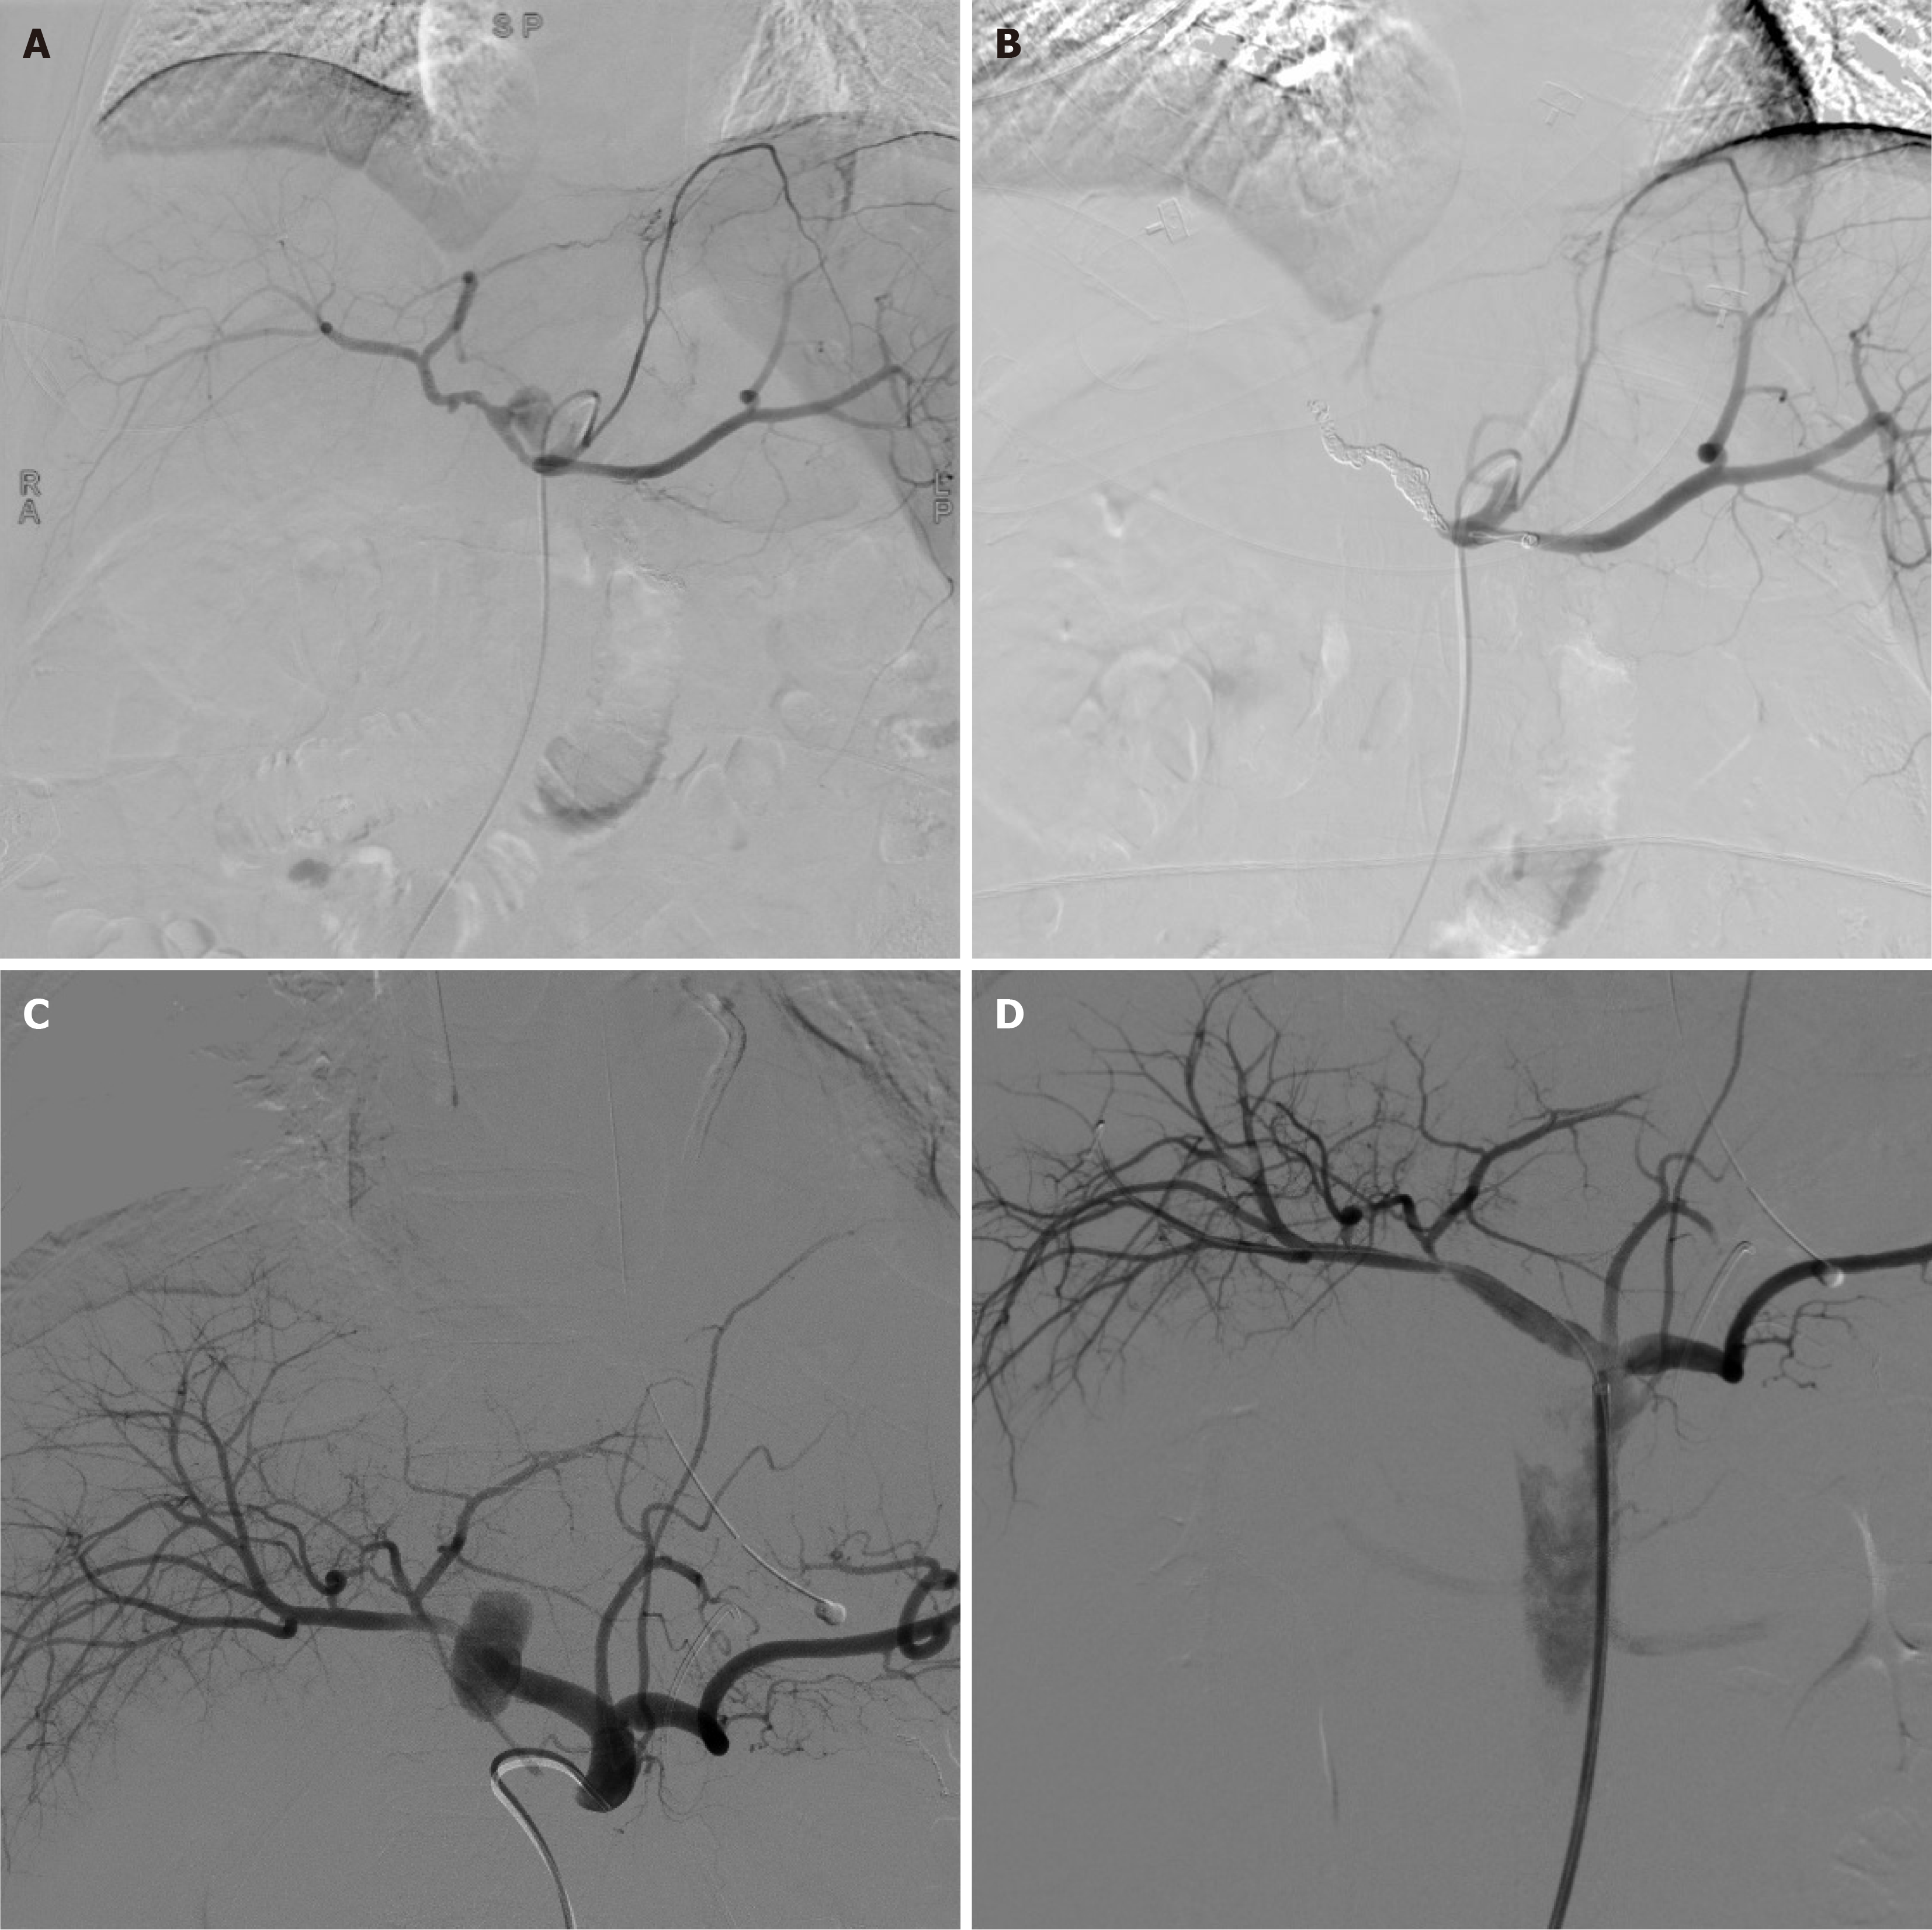

Figure 2 Endovascular management of post-pancreaticoduodenectomy arterial pseudoaneurysms.

A and B: A 61-year-old male patient who underwent radical pancreaticoduodenectomy for bile duct cancer presented with acute hemorrhage from the gastroduodenal artery stump on postoperative day 27. Conventional hepatic angiography demonstrated a large pseudoaneurysm at the gastroduodenal artery stump with active contrast extravasation, associated with a drop in hemoglobin concentration (A); targeted embolization of the common hepatic artery achieved successful hemostasis (B); C and D: A 62-year-old male patient underwent radical pancreaticoduodenectomy combined with segmental resection of the transverse colon for a duodenal malignancy. Postoperatively, he developed intra-abdominal infection and presented with gastrointestinal bleeding on postoperative day 14, receiving both interventional treatment and laparotomy for debridement and drainage. The patient ultimately died from respiratory failure on postoperative day 77. Digital subtraction angiography revealed a pseudoaneurysm of the common hepatic artery (C); after placement of a covered stent in the common hepatic artery, follow-up angiography confirmed complete exclusion of the pseudoaneurysm while preserving distal hepatic arterial flow (D).